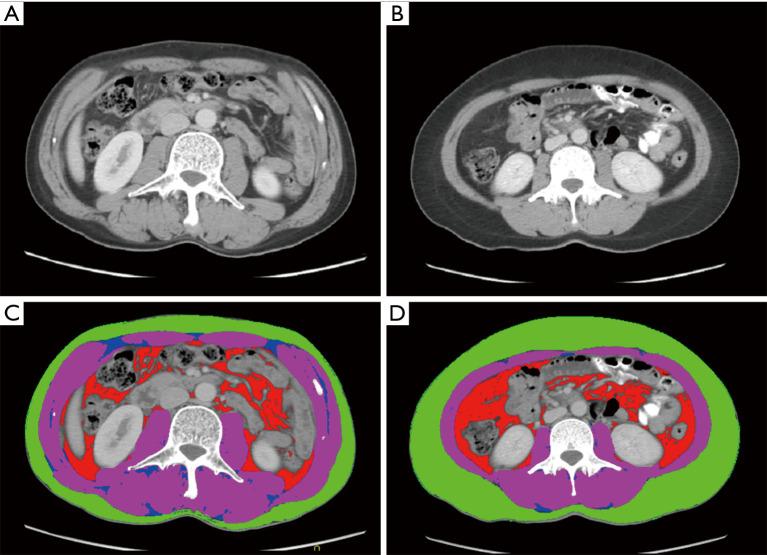

METHODS

GC patients undergoing radical gastrectomy in the single center from January 2012 to December 2023 were retrospectively included. Patients with distant metastases or other malignant tumors before the surgery were excluded. Included patients were divided into the liver metastasis and control groups according to the presence of liver metastasis within the 3-year follow-up. Body compositions including skeletal muscle (SM), visceral adipose tissue (VAT), subcutaneous adipose tissue (SAT), and intramuscular adipose tissue (IAT) were estimated using preoperative computed tomography (CT) images at the L3 level. Multivariate logistic regression analysis was used to identify the independent risk factors of liver metastasis. Receiver operating characteristic curve was used to evaluate the predictive performance of significant factors.

回顾性纳入2012年1月至2023年12月在单中心接受根治性胃切除的GC患者。排除术前有远处转移或其他恶性肿瘤的患者。根据3年随访期间是否存在肝转移,将纳入的患者分为肝转移组和对照组。使用术前L3水平的计算机断层扫描(CT)图像评估包括骨骼肌(SM)、内脏脂肪组织(VAT)、皮下脂肪组织(SAT)和肌内脂肪组织(IAT)在内的身体组成。采用多因素逻辑回归分析确定肝转移的独立危险因素。使用受试者工作特征曲线评估显著因素的预测性能。